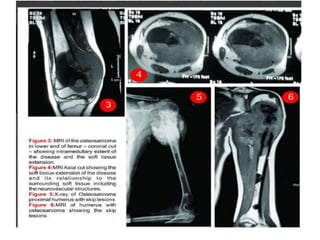

Magnetic Resonance Imaging

• tumor involvement and extent within the marrow

• provides details of soft-tissue extension

• Relation with neuro-vascular bundle

• Skip lesion